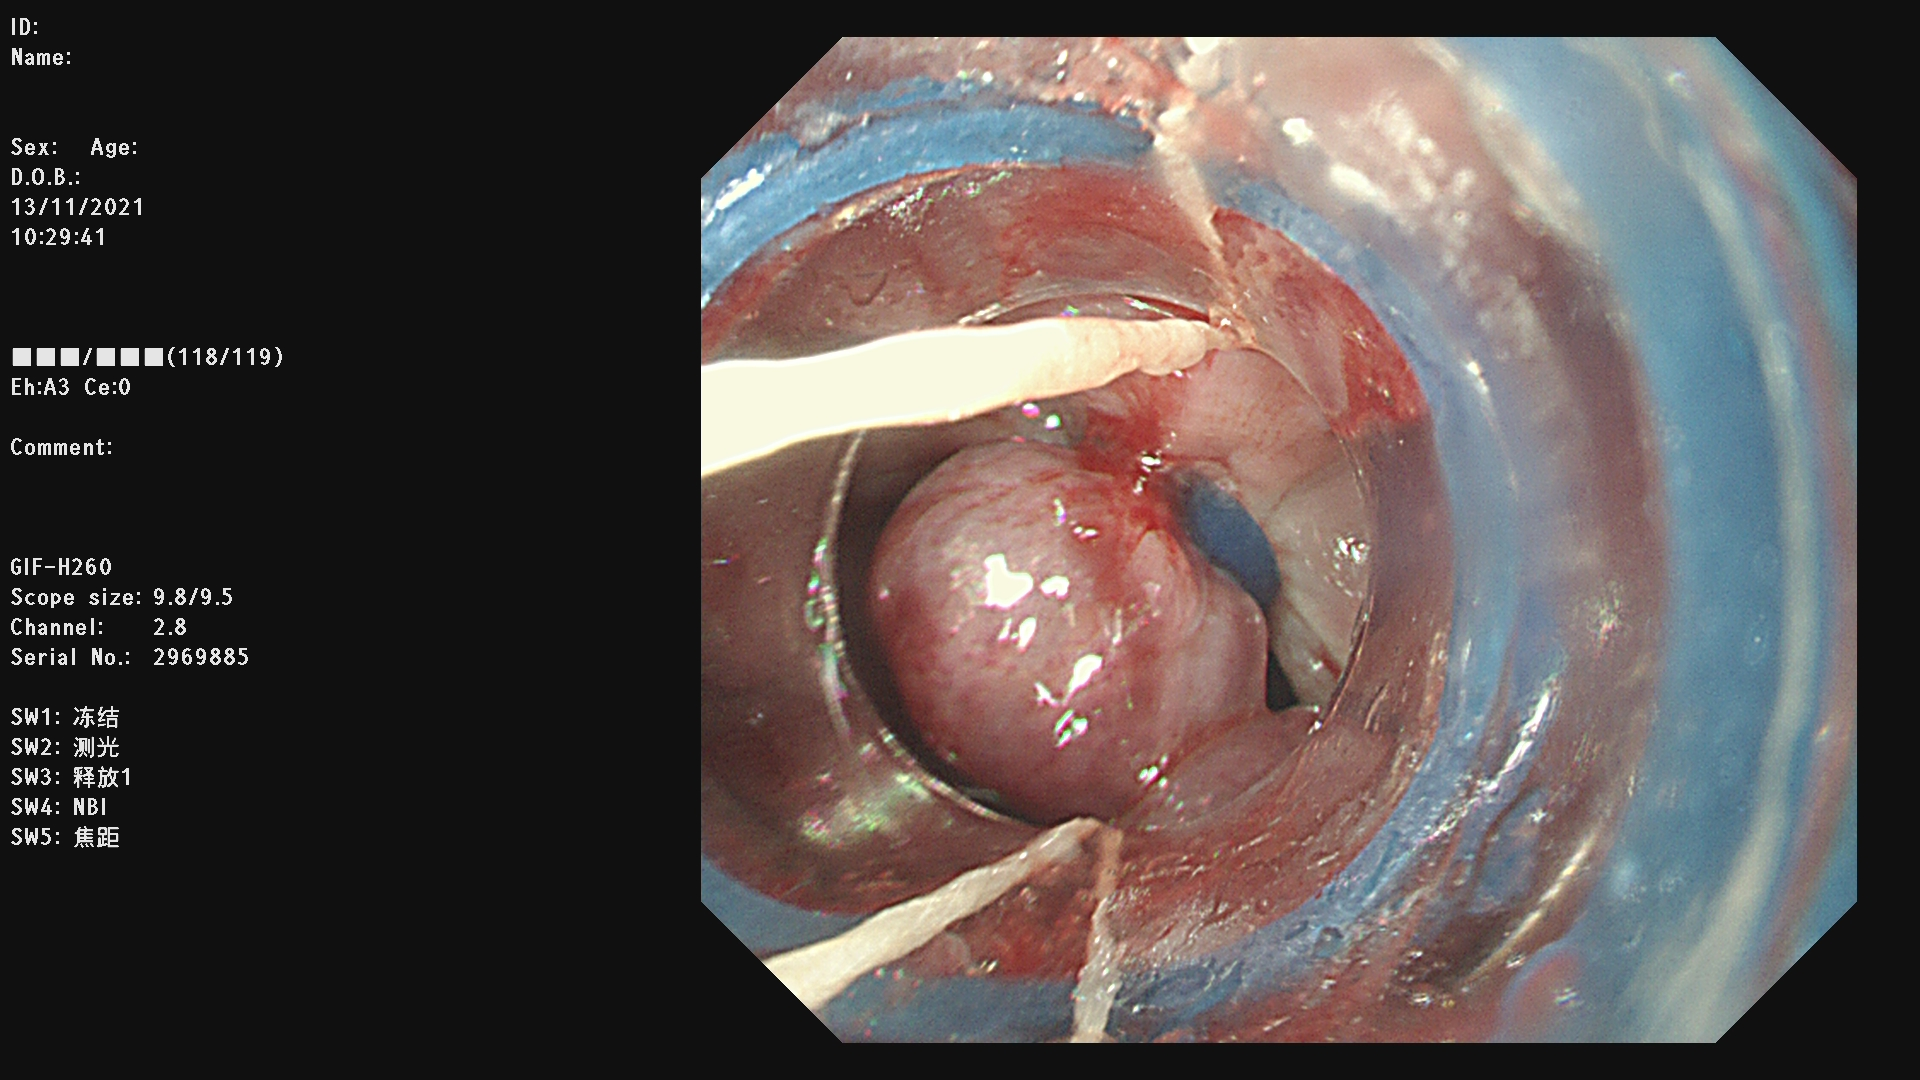

内镜下食管静脉曲张套扎术简称EVL,是一种安全有效的治疗食管静脉曲张破裂出血以及预防出血的方法。EVL具有操作简便、创伤小、安全性高,疗效确切、可重复进行的优点。

内镜下硬化术(EIS)是通过内镜下注射硬化剂和/或组织胶治疗急性食管胃底静脉曲张破裂出血及预防再出血的方法。

例一 :